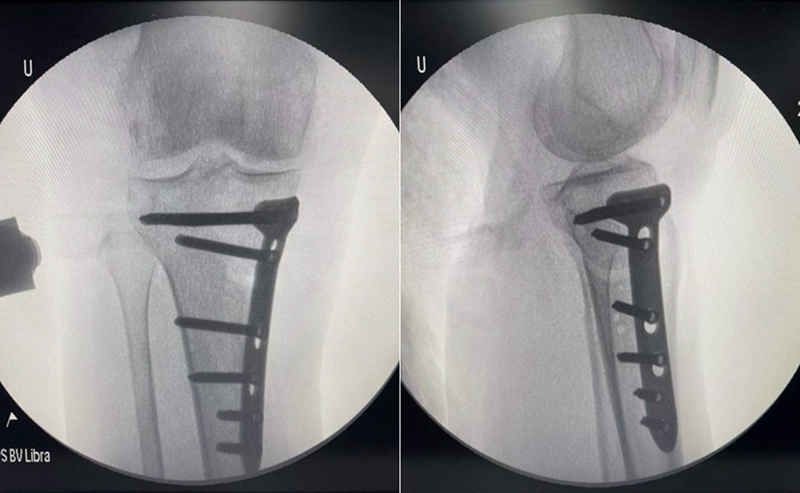

术中关节镜证实外侧软骨良好,取出游离体,内侧清理后行胫骨高位截骨术。

术后影像

因此,术中用关节镜在髁间窝和髌上囊分别取出了两枚游离体,术中也验证了MR显示的外侧关节面水肿区不是位于外侧间室的负重区,关节镜下外侧软骨为全层软骨,软骨退变区位于股骨滑车沟外侧近潮线处,内侧软骨磨损,部分裸露。故在内侧清理后加做HTO,将力线调整至55%。术者相信这是最利于患者的治疗选择。